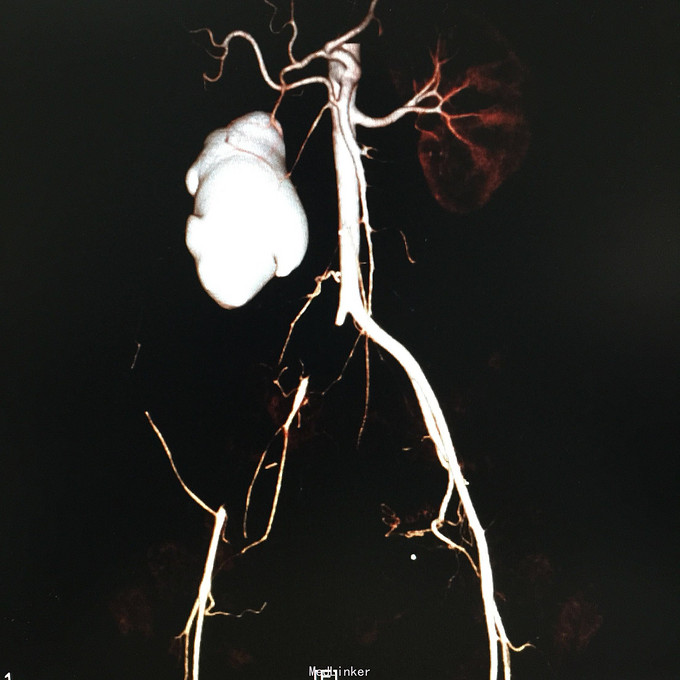

查体无特殊。 辅助检查:中下腹CT平扫+增强+CTU+CTA示:1.右输尿管中上段病变,考虑恶性病变,周围多发淋巴结转移,髂总动脉及髂外动脉起始部、髂内动脉中上段受侵闭塞,右侧腰大肌可疑受侵;建议输尿管镜检查;右肾重度积水,右肾功能明显受损。2.CTA示:右肾动脉纤细,肝右动脉起源于肠系膜上动脉。3.子宫体密度不均匀,建议MRI检查。中下腹MRI平扫+增强+MRU检查结果类似。

患者术后2月出现反复臀部疼痛,左侧为主,疼痛跑迷宫为隐痛,于翻身及活动时加重,卧床休息可稍缓解,多于下午出现,伴有发热,最高达39℃,在当地医院予“氟康唑”及止痛治疗后稍有缓解,但仍反复发热。后疼痛加剧,并出现双下肢疼痛,以大腿外侧为主,无间歇性跛行,无小腿及双足麻木疼痛不适,行对症治疗后效果不佳,于2015-10-9再次返院,予消炎止痛、营养支持及营养神经等治疗。查CT及MRI均提示骶髂关节炎症及腹膜后巨大病变,右侧髂总动脉及髂内、外动脉上段、右侧腰大肌受累。2015-10-15 14:00患者出现右下肢剧烈疼痛、右下肢乏力和麻木,随后出现2次血便,每次量约100ml,暗红色,无腹胀、腹痛等不适,查血提示白细胞 28.17*10E9/L,中性粒绝对值 25.33*10E9/L,血红蛋白56g/L,予止血、输血、抗真菌、止痛等治疗。19:00再次出现右下肢剧烈疼痛伴右下腹痛,查体:BP 80-90/50-60mmHg,P 100-106次/分,R 23次/分,SpO2 100%。右下腹轻压痛,反跳痛阴性,右下肢蹲背伸及踝背伸肌力II-III级,立即行全腹CT检查,示右髂总动脉假性动脉瘤破裂,予加强输注浓缩红细胞及补液支持治疗。清介入科会诊,考虑脓肿和感染为介入血管腔内支架置入治疗的禁忌症,建议予血管外科行开放手术,予患者及家属沟通,并转外院血管外科进一步治疗。